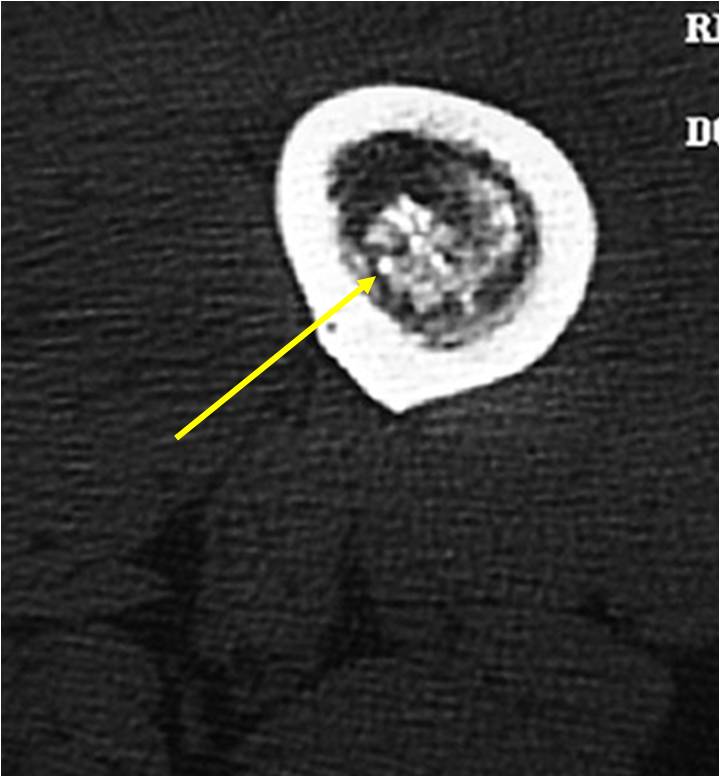

- Localized, radiolucent defect usually with punctate calcifications

- Calcifications are stippled, punctate, popcorn like calcifications and “Ring and Arc” calcifications

- Cartilage tumors grow in a lobular manner. The perimeters of the lobules undergo

- enchondral ossification that may calcify. If the entire perimeter of the lobule calcifies it appears

- radiographically as a “Ring”. If a portion of the perimeter of a lobule calcifies it forms an “Arc” on

- an X-ray.

- Chondroid matrix with calcifications in majority of tumors

- Calcified chondroid – low intensity all sequences

MRI:

- Lobulated margin (Lobular Growth Pattern)

- T1 Weighted Images: Intermediate Signal Intensity

- Calcifications will be low signal

- T2 Weighted Images: High Signal Intensity

- High water content shows as high signal on T2 weighted images

- Marked increased intensity long TR images